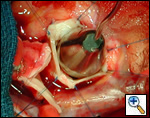

Pulmonary homograft or pericardial patches (tanned in glutaraldehyde) for the “shields”. These patches should not be too large – this will lead to aortic insufficiency.

First coronary sinus incision in noncoronary sinus to facilitate exposure of the incisions into the coronary orifice sinuses.

In most cases, the right coronary artery sinus should be opened to the left of the coronary orifice and the left coronary artery sinus to the right of the coronary orifice. Occasionally one may not have enough room between a coronary orifice and the aortic valve; in this case the incision site should be tailored to the situation.

Ensure similar orifice sizes between the proximal and distal ascending aorta after patch augmentation by the use of a sizing dilator.